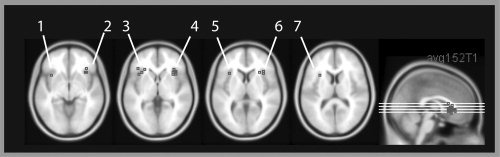

For the mid‐VLPFC, a different approach had to be taken because no established localizer task exists to define participant‐specific ROIs in these areas. To this end, ROIs were defined using data from a previous study [Dove et al., 2006]. A random effects group analysis was carried out contrasting conditions in which participants were asked to intentionally encode or recognize abstract paintings with conditions in which the viewing of abstract paintings was passive – i.e. the identical manipulation to that used in the current study albeit with only abstract painting stimuli. The results showed increased mid‐VLPFC activation in the high‐intention condition. ROIs for the current study were generated by drawing 7 mm spheres around the peaks using the MARSBAR tool [Brett et al., 2002]. These spheres were somewhat smaller than the whole activation cluster, to ensure that only voxels with relatively high t‐values would be chosen in the current experiment. Note that we choose a sphere here rather than a single voxel because the ROI could not be defined for each volunteer individually, as in the FFA and PPA. Choosing a larger ROI makes it more likely that the ROI of an individual volunteer contains voxels that show activity in the experimental conditions. The MNI coordinates of the peak activation were 36, 22, −4 in the right mid‐VLPFC and −36, 16, −4 in the left mid‐VLPFC (Fig. 3).

Figure 3.

Peak activity in the mid‐ventrolateral prefrontal cortex or anatomically close to the mid‐ventrolateral prefrontal cortex in studies with different cognitive demands, overlaid onto a normalized and averaged structural image in MNI space (MNI 152 image from the SPM distribution). The figure was created using MRIcro by Prof. Chris Rorden. References 1–7 refer to Table I.

The mid‐VLPFC showed higher signal intensity in the high intention conditions compared with the low intention conditions. Whilst this finding could be due to differences in response selection during recognition (volunteers have to select a response in the high intention recognition condition, but press two buttons during the low intention re‐viewing condition), this hypothesis cannot explain the results during encoding. Therefore, we suggest that this pattern of activity reflects differences in cognitive control processes between the conditions. In addition to the work of Petrides [1994] and others, this result ties in well with the view that the mid‐VLPFC is activated under a wide variety of conditions that require control processes (Fig. 3 and Table I; [Braver et al., 2003; Bunge et al., 2001; Cadoret et al., 2001; Cools et al., 2002; Dove et al., 2000, 2006; Duncan and Owen, 2000; Houde et al., 2000; Jenkins et al., 1994; Kostopoulos and Petrides, 2003; Langleben et al., 2005; Turk et al., 2004]). Note that the coordinates reported in these studies are anatomically very close to the centre of our regions of interest in the mid‐VLPFC (Fig. 3 and Table I). As pointed out in the introduction, “mid‐VLPFC” activity as defined in this paper spreads from the outer surface of the frontal operculum to become continuous with reported activity in the anterior insula [Duncan and Owen, 2000]. One of our ROI, in the right mid‐VLPFC is more clearly located in the frontal operculum, whereas the other ROI is somewhat closer to the anterior insula. Both ROIs, however, show the same pattern of results. One account is that activation that may appear to be in the anterior insula could in fact be slightly misplaced frontal operculum activity. This would conform to “mid‐VLPFC,” according to Duncan and Owen's definition [Duncan and Owen, 2000]. An alternative account is that the activity stems from the anterior insula, which is showing the same modulatory pattern as the “mid‐VLPFC.” It would be interesting to clarify this question in future studies.